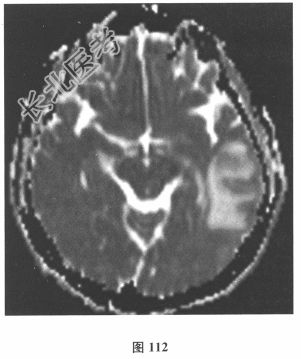

- 简答题2、脑脊液检查:常规、生化均正常,CSF-病毒TORCH(-),抗Hu、Yo、Ri均阴性,OB、MBP正常。血清抗Hu、Yo、Ri均阴性。颅脑MRI显示左颞枕、右顶枕多发长T₁、长T₂信号,Flair高信号,病变累及皮质及皮质下白质,病灶无强化,见图108~图114。根据颅脑MRI,需要鉴别的疾病应是